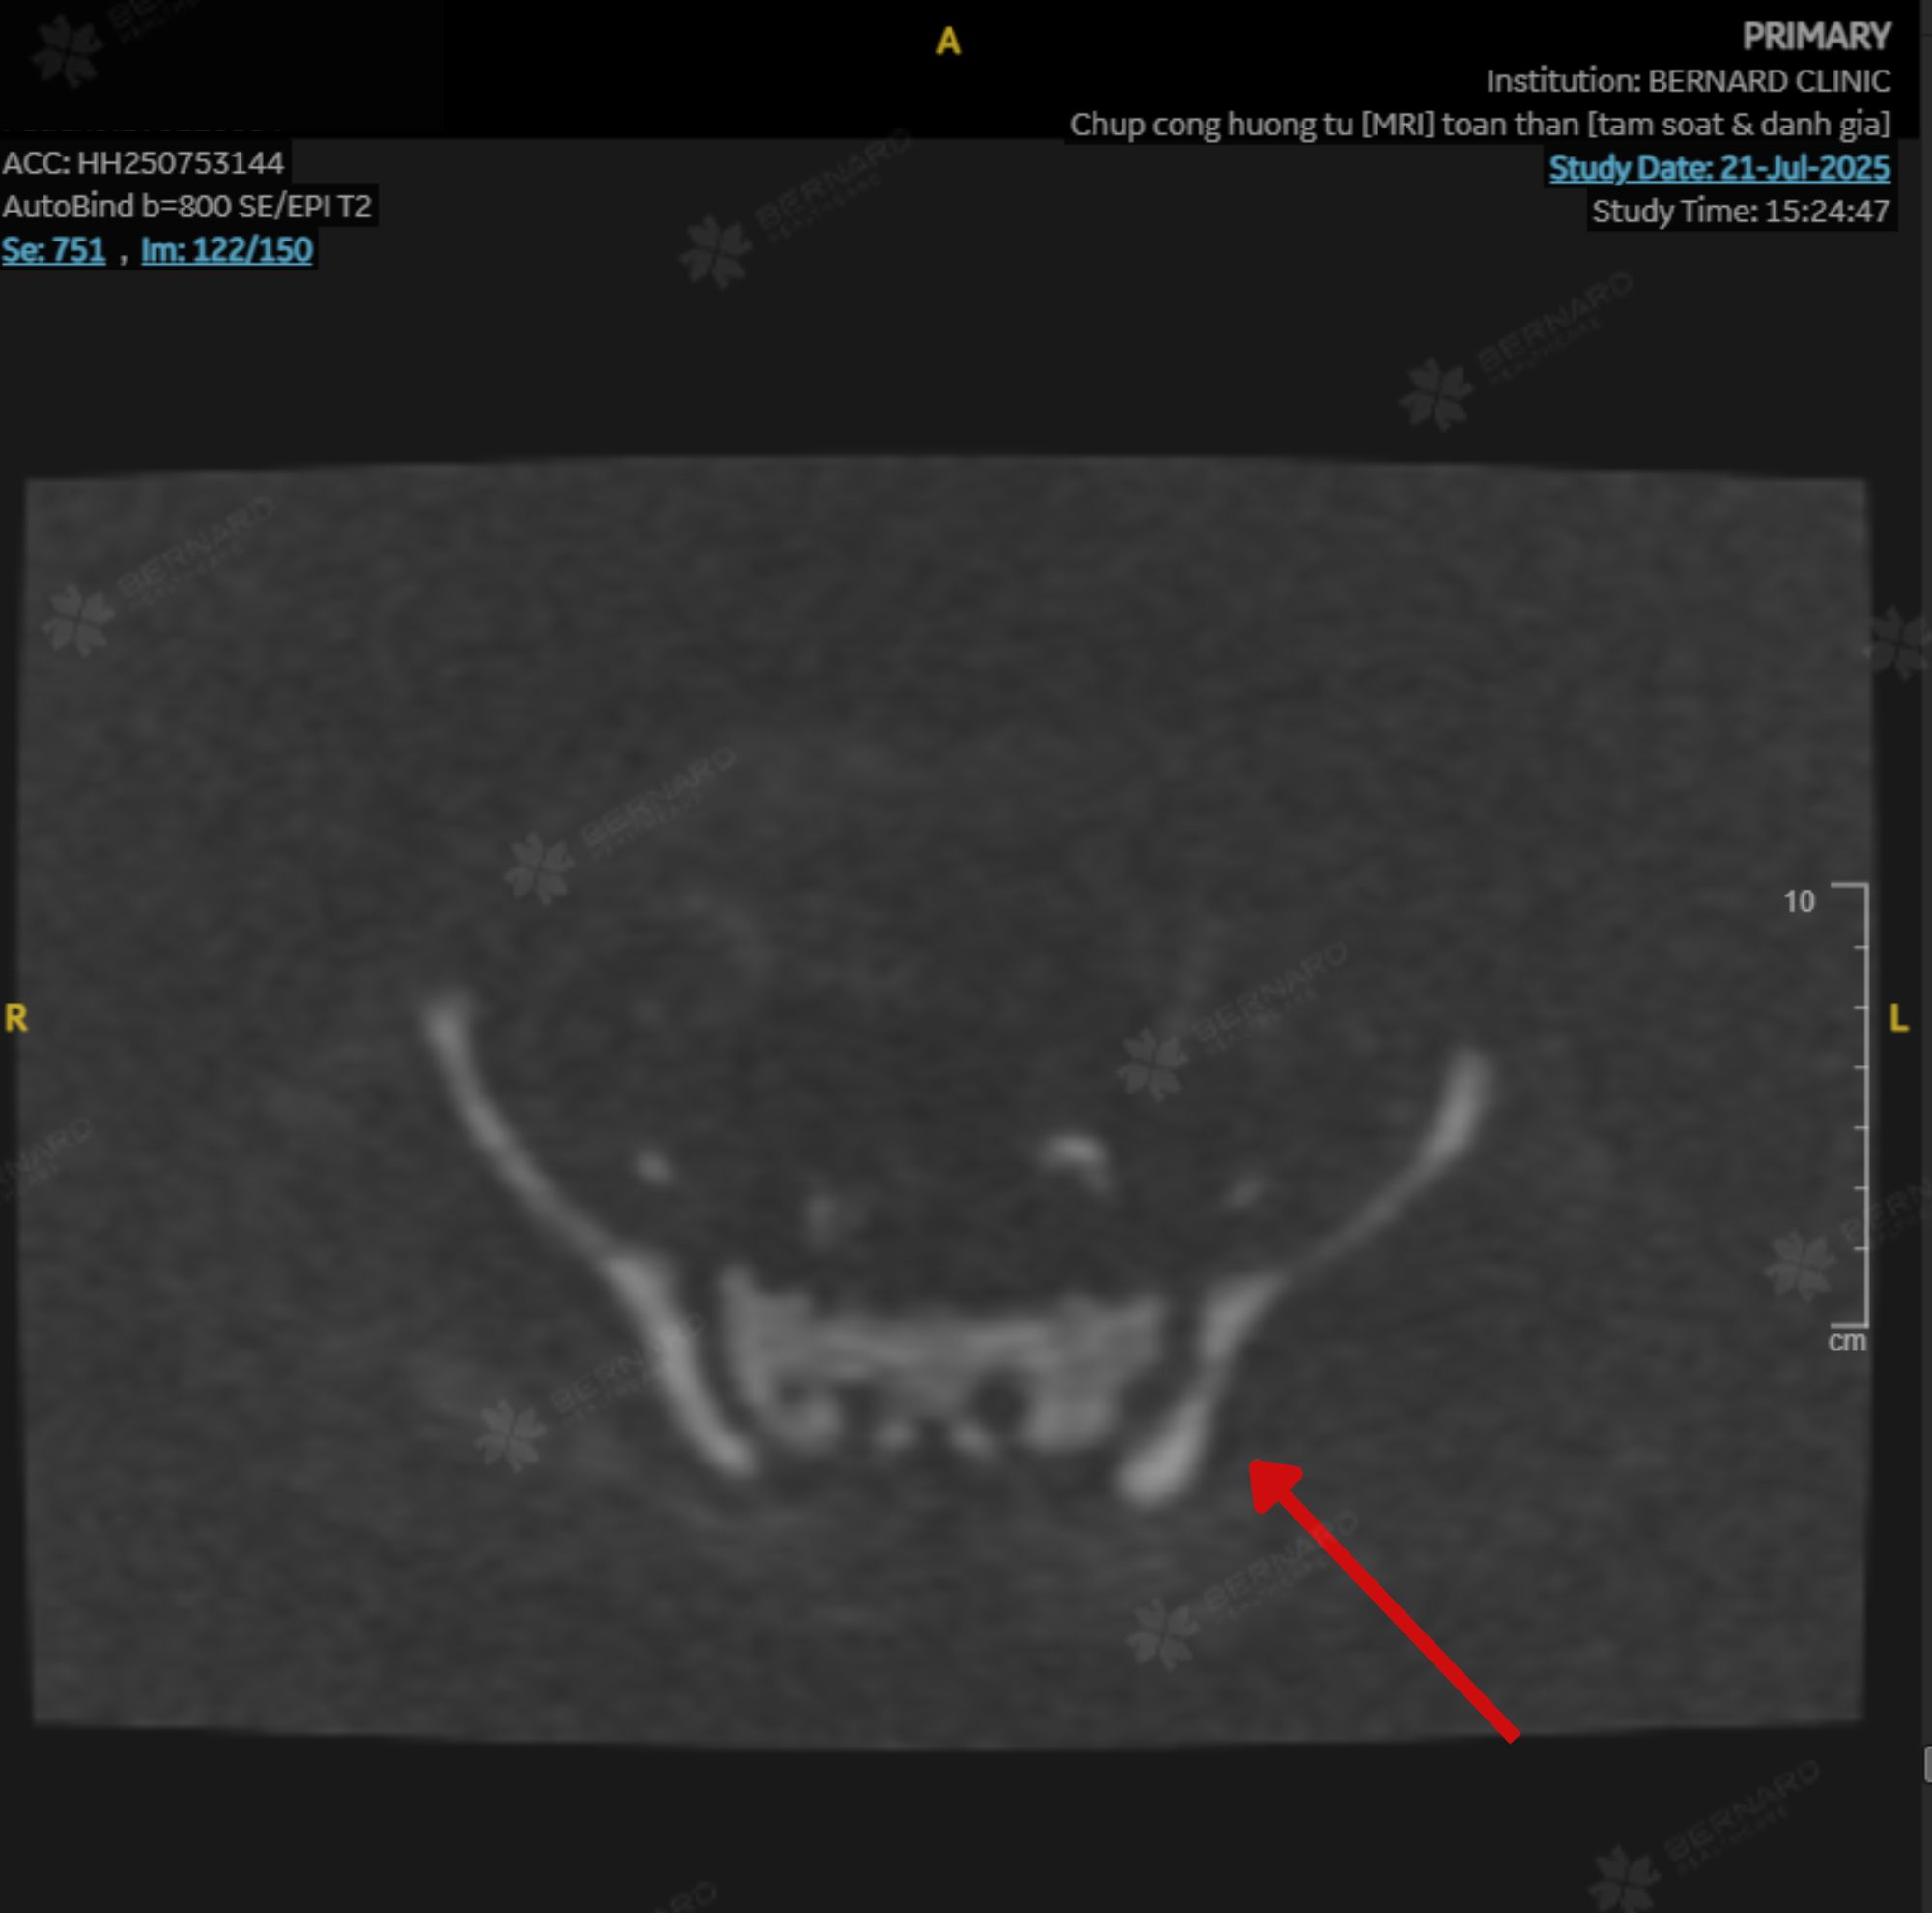

Kết quả MRI toàn thân ghi nhận thay đổi tín hiệu tủy xương tại nhiều vị trí như cột sống, xương sườn, xương chậu, đầu trên xương đùi và vùng lách. Những đặc điểm hình ảnh này gợi ý tăng sản tủy xương (bone marrow hyperplasia) - tình trạng tủy hoạt động mạnh hơn bình thường.

Đây có thể là dấu hiệu của một số bệnh lý huyết học, trong đó có nhóm bệnh tăng sinh tủy, nhưng cũng có thể gặp ở các tình trạng lành tính như thiếu máu mạn hoặc viêm kéo dài.

Theo quy trình Ningen Dock chuẩn Nhật, toàn bộ hình ảnh MRI của chị được kiểm tra chéo bởi chuyên gia Bệnh viện Đại học Yamanashi (Nhật Bản). Báo cáo phản hồi đồng thuận với nhận định ban đầu và khuyến nghị bệnh nhân tiếp tục được đánh giá bởi chuyên khoa huyết học để làm rõ nguyên nhân.

Hiện công thức máu của chị vẫn trong giới hạn bình thường. Tuy nhiên, bác sĩ cho biết tăng sản tủy xương là bất thường cần theo dõi sát để không bỏ lỡ giai đoạn rất sớm của bệnh lý huyết học nếu có.